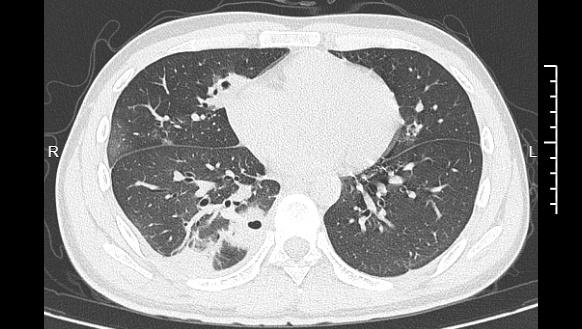

熬到第三天,小林已经烧到39℃,赶紧去医院就诊。接诊的主任医师丁群力一看他的症状,立刻安排了ct检查。结果显示:小林的肺里有十几个空洞,部分肺组织已经坏死,这是典型的血源性肺脓肿。

小林的ct影像显示肺里有多个空洞